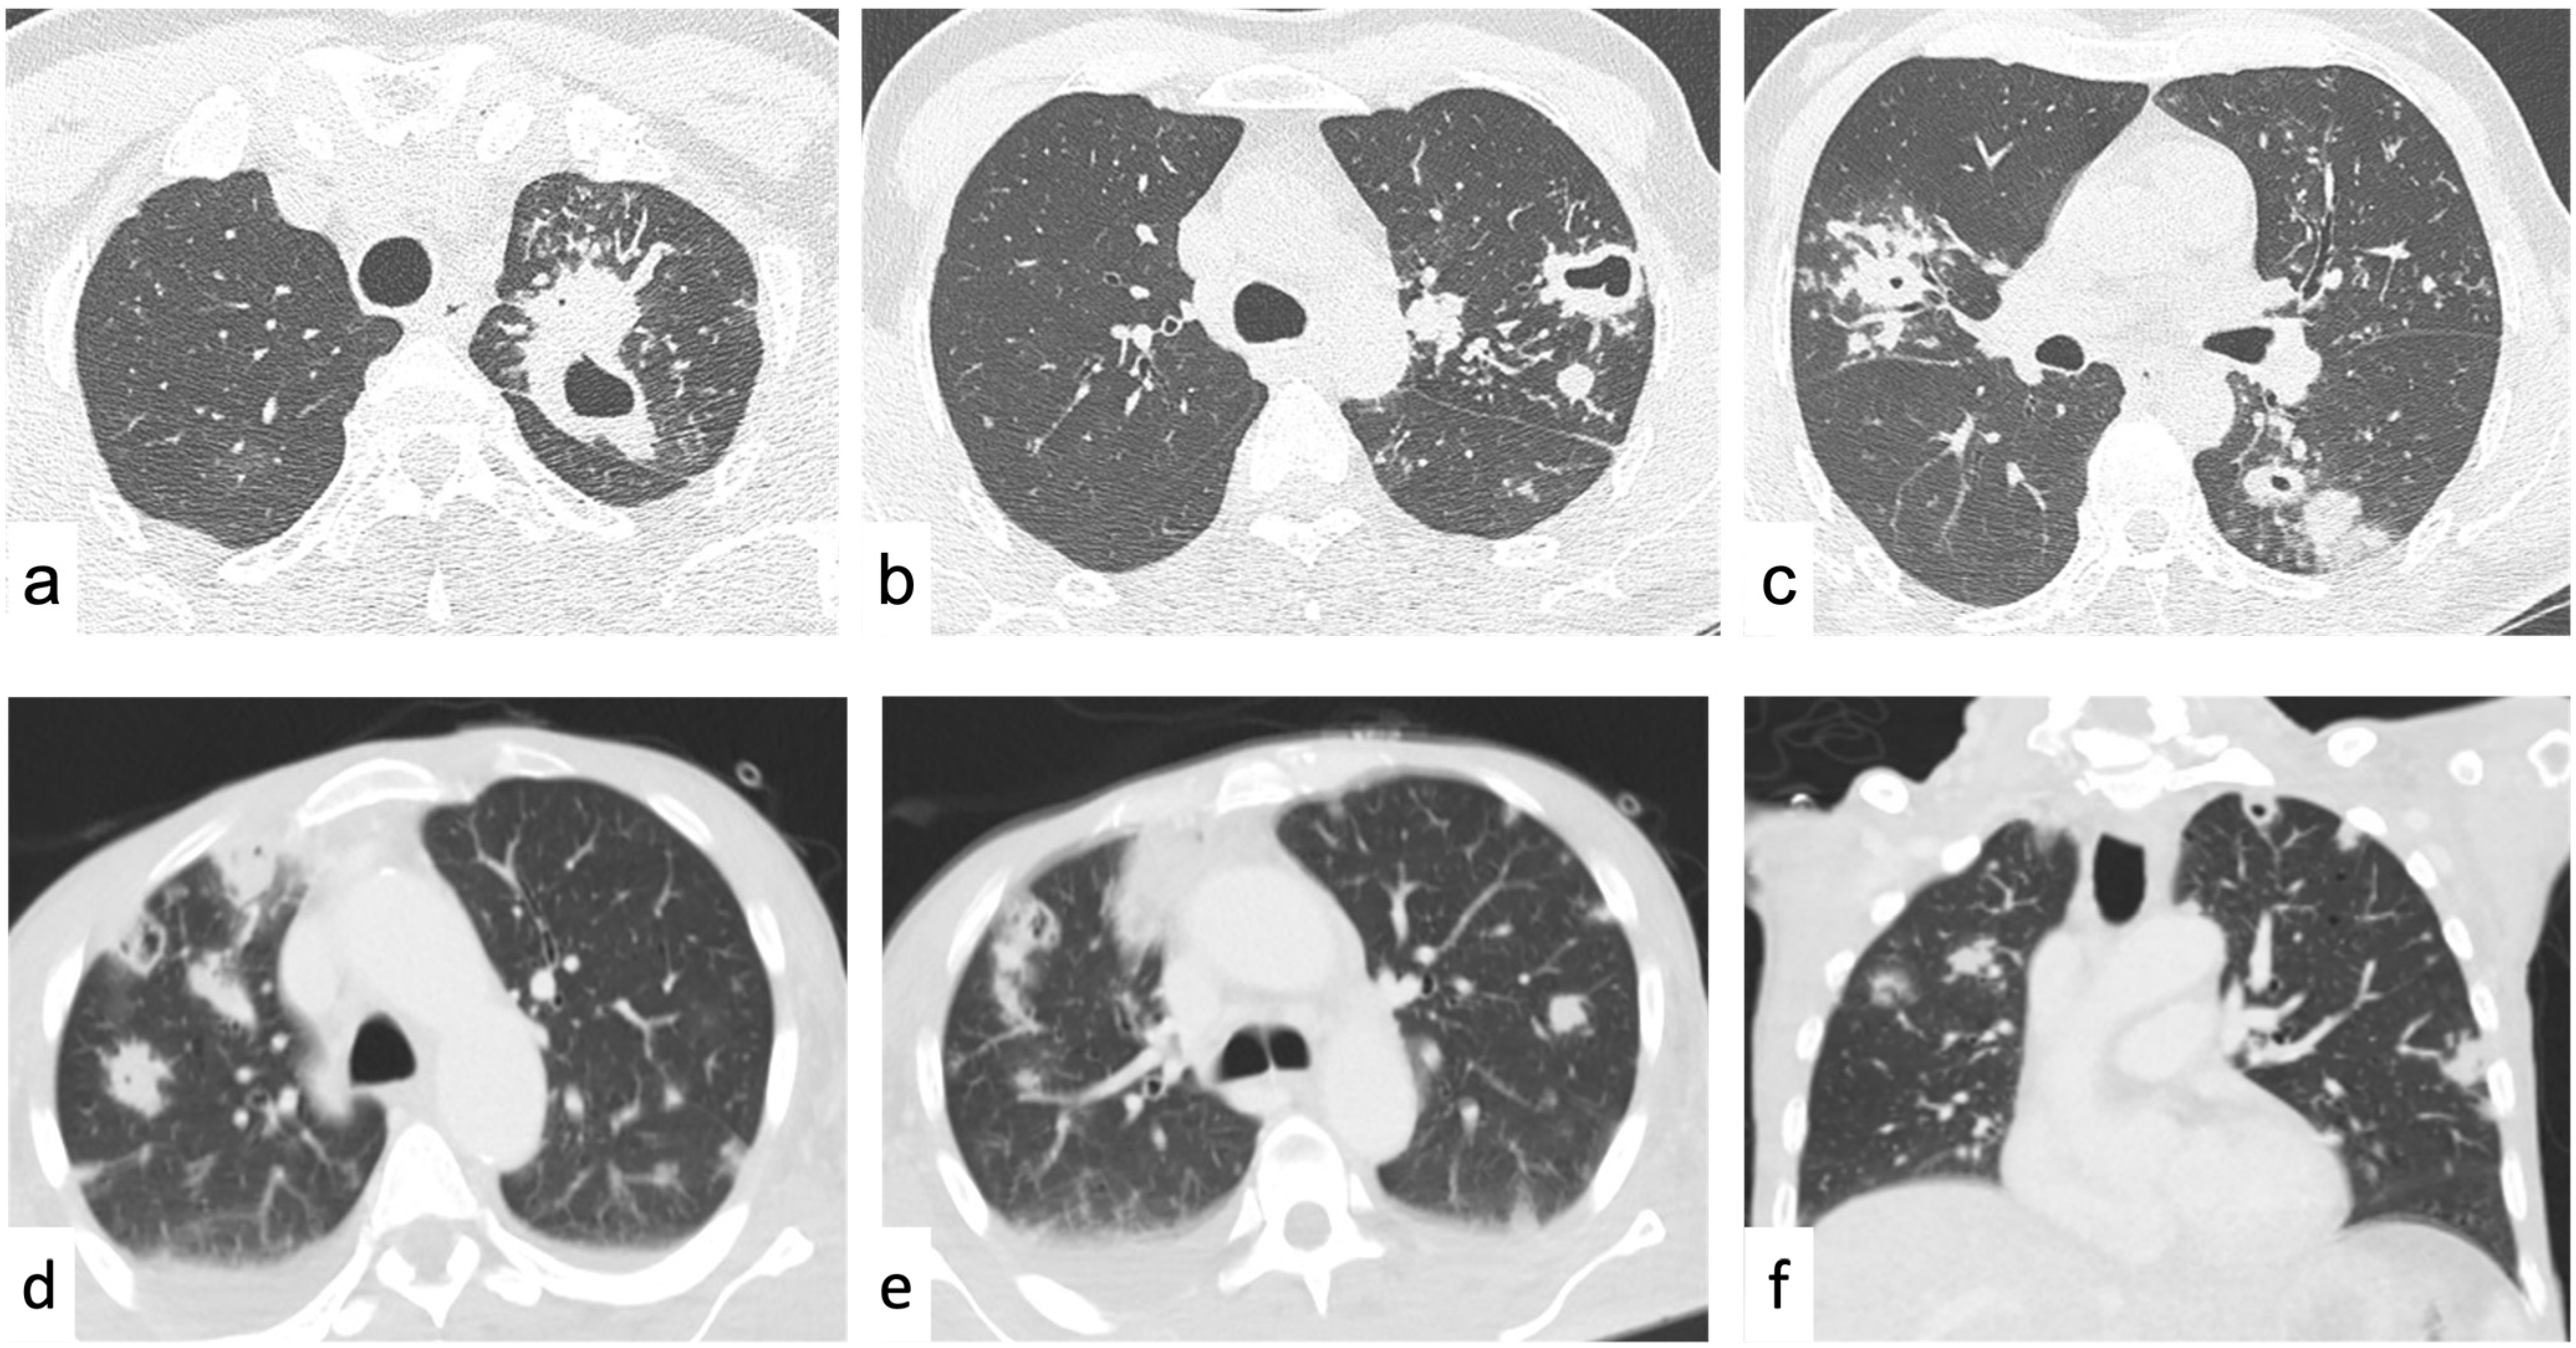

4.2. Diffuse Lung Disease

4.2.1. Reticular Pattern

Interlobular Septal Thickening

4.2.2. Nodular Pattern

Perilymphatic Nodules

Centrilobular Nodules

Random Nodules

4.2.3. Increased Lung Attenuation

Ground-Glass Opacities

Consolidations